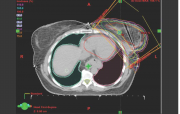

| 12:27, 3 במרץ 2015 | Irradiation4.png (קובץ) |  |

158 קילו־בייטים | Motyk | 1 | |

| 20:10, 2 במרץ 2015 | Irradiation3.png (קובץ) |  |

150 קילו־בייטים | Motyk | 1 | |

| 19:38, 2 במרץ 2015 | Irradiation2.png (קובץ) |  |

217 קילו־בייטים | Motyk | 1 | |

| 19:34, 2 במרץ 2015 | Irradiation1.png (קובץ) |  |

468 קילו־בייטים | Motyk | 1 | |

| 06:47, 1 במרץ 2015 | Radiotherapy2.png (קובץ) |  |

231 קילו־בייטים | Motyk | 1 | |

| 06:41, 1 במרץ 2015 | Radiotherapy1.png (קובץ) |  |

261 קילו־בייטים | Motyk | 1 | |